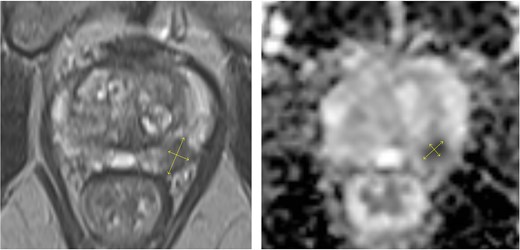

A 77-year-old male without relevant comorbidities and not on anticoagulant therapy was referred for prostate biopsy after PSA increased from 4.5 to 8.1 ng/ml over 6 months. Multiparametric magnetic resonance imaging (MRI) demonstrated moderate benign prostatic hyperplasia (5.0 × 3.7 × 4.1 cm; 38 ml) and a PI-RADS 4 lesion (11 × 6 mm) in the mid-third of the left peripheral zone, dorsolaterally. The lesion showed hyperintensity on diffusion-weighted imaging (DWI) and hypointensity on T2-weighted sequences, consistent with restricted diffusion (Fig. 1). A 15-core systematic transrectal MRI/ultrasound fusion biopsy was performed after intravenous administration of ertapenem (1 g). The patient experienced unusually intense pain during the procedure that regressed spontaneously. A post-biopsy rectal examination revealed no evidence of significant bleeding.

Multiparametric MRI of the prostate showing an 11 × 6 mm PI-RADS 4 lesion in the mid-third of the left dorsolateral peripheral zone with marked hypointensity on T2-weighted and diffusion-weighted images.